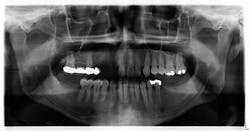

He fell 25 feet while working on a crane, lost consciousness, and underwent cranioplasty surgery for a skull fracture. Furthermore, he had teeth nos. 1, 6, 7, 16, 17, 18, 19, 31, and 32 removed (figure 1). A workers’ compensation claim was filed as the patient understandably wanted his teeth fixed, replaced, and back to the status quo prior to the injury. Seems simple, right? Wrong. Sooooooo wrong.

A healthy 31-year-old male reports that besides a visit to the dentist four years ago to have a bridge done on the upper right side, any previous dental visits occurred when he was around 14–15 years old. Upon initial examination with radiographs (by a previous dentist shortly after the accident), it was determined that the patient had caries on teeth nos. 8, 9, 12, 13, 15, and 30 with advanced, generalized class III periodontal disease. Interestingly enough, it was also determined that the patient was “totally temporarily disabled” for one week following his surgery and extractions. One week.